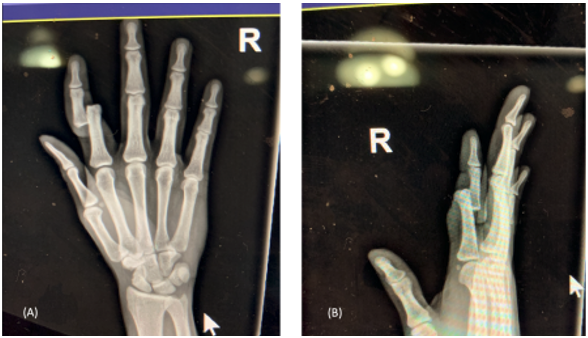

A 24-year-old male presented to the emergency department with an open, right index finger injury that occurred while playing basketball (Figure 1). Sensation and perfusion to the patient’s hand were noted to be intact. Bedside reduction under digital block was attempted without success. Given the irreducible nature of his dorsal proximal interphalangeal joint (PIPJ) dislocation, the patient was taken to the operating room for washout and reduction. A volar approach to the joint confirmed a dorsal PIPJ dislocation with disruption of the volar plate and collateral ligaments. The flexor digitorum superficialis (FDS) and flexor digitorum profundus (FDP) tendons were displaced to the radial side of the proximal phalangeal head (Figure 2). These could be seen acting as a noose on the neck of the proximal phalanx with attempted reduction. The index finger was flexed to reduce tension on the FDS and FDP tendons. The FDS was repositioned volar to the phalangeal head followed by the FDP. Gentle traction was then placed on the finger with subsequent reduction of PIPJ. Passive range of motion demonstrated a stable reduction with supporting evidence of static and live orthogonal fluoroscopic views (Figure 3). The patient was started on immediate active motion postoperatively with buddy taping of the index to the middle finger. Active motion was as tolerated with the guidance of a certified hand therapist once per week. At 3 months postoperatively, he had full flexion of the finger with a 10-degree contracture at the PIP joint. He returned to work and recreational activities with no limitations.